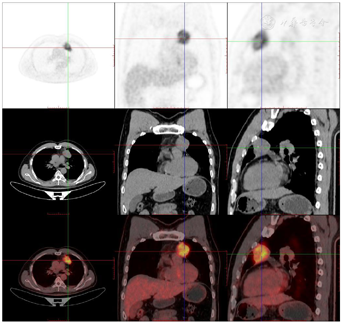

头颅顶可见术后瘢痕,愈合可,后颈可见一长约10 cm术后愈合瘢痕。头颅压痛、包块。发病来,患者神志清,精神可,睡眠可,饮食及大小便正常,体重无明显变化。2021年10月8日行PET-CT示左侧额顶部颅骨术后改变;左侧颞极片状高密度影并邻近骨质破坏,代谢增高(图A);左前纵膈肿块,代谢增高(图B);双肺散在结节,代谢轻度增高(图C);右侧锁骨、左侧第6肋,胸9-腰1、3椎体及其附件骨、双侧髂骨及双侧股骨近端多发混合型骨质破坏,代谢不同程度增高,考虑多发转移瘤(图D,图E,图F);2021年10月10日复查CT示右肺下叶可见结节影,直径约1.5 cm,增强扫描轻度强化;前上纵膈可见类圆形软组织密度影,边界清楚,大小约4.4 cm×3.3 cm,增强扫描轻度强化。于2021年10月11日在局部浸润麻醉下行CT引导下经皮纵膈占位穿刺活检术。病理结果示:肺穿刺组织内见恶性肿瘤,符合转移性间变性脑膜瘤。2021年10月13日MRI示:多发胸椎椎体及附件、所扫及L1椎体异常信号,结合病史,考虑为转移瘤可能。